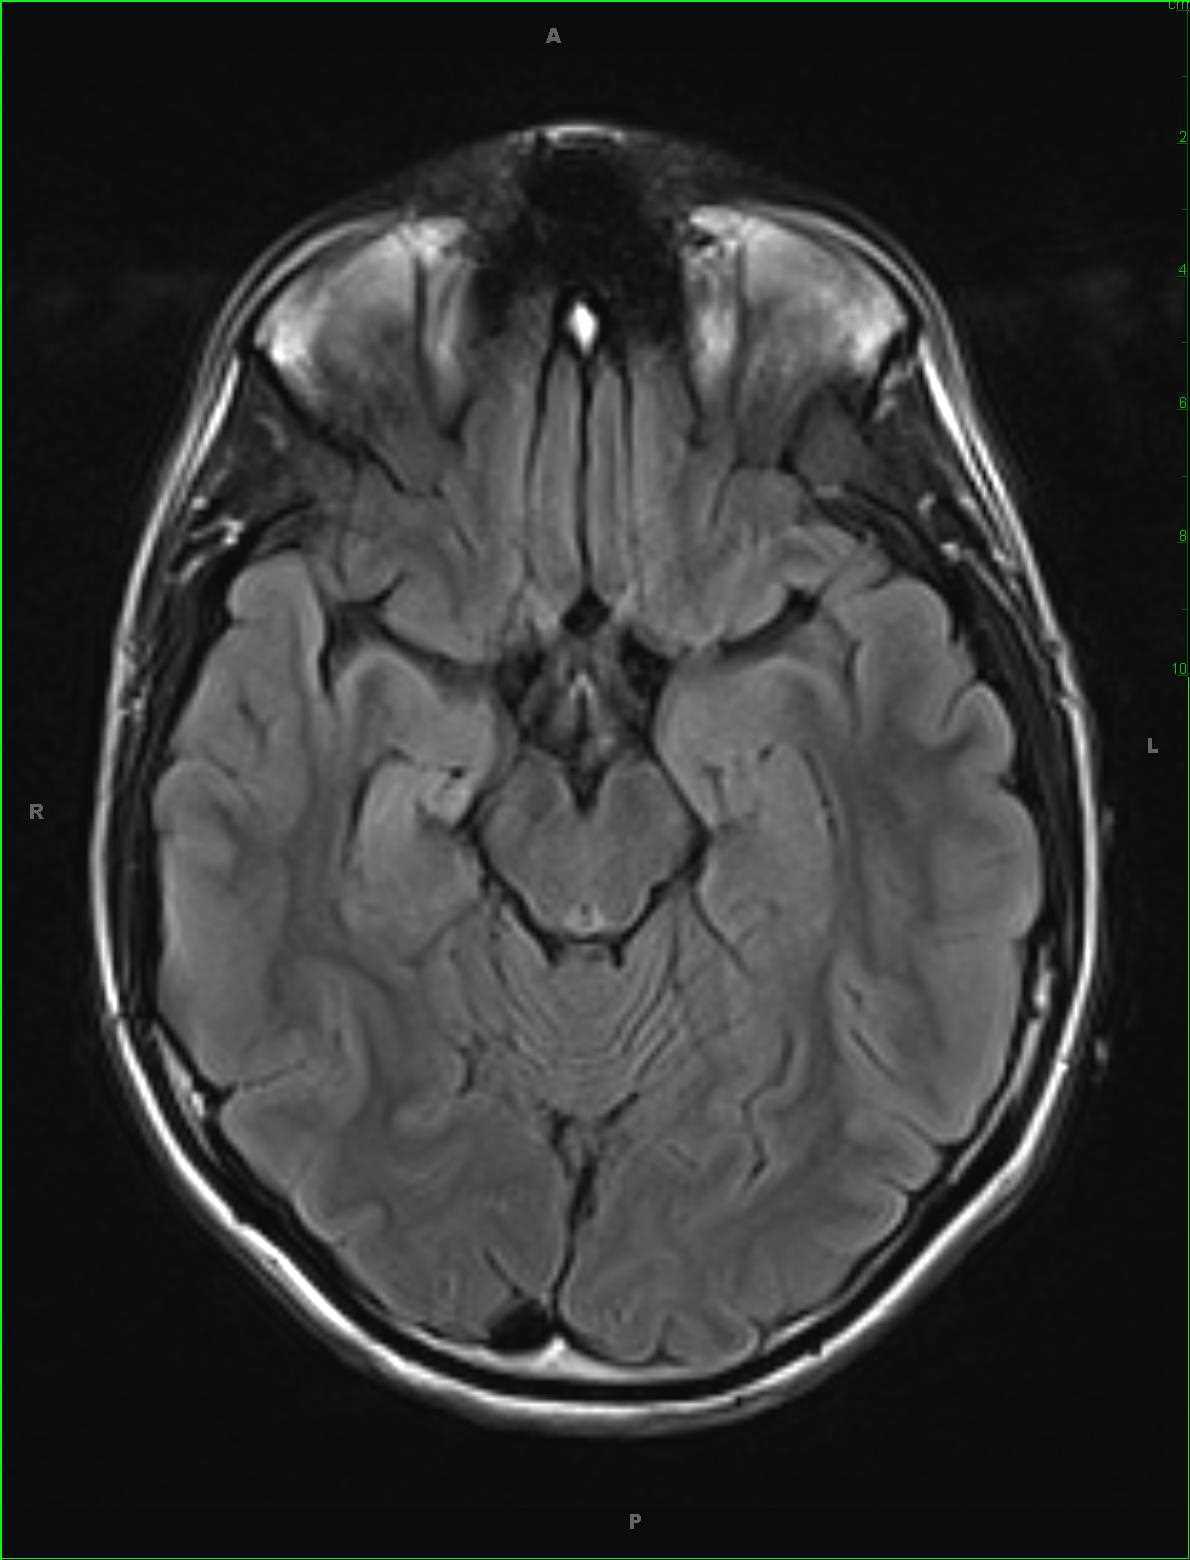

Inferior Right Temporal Encephalocele

32-year-old male with a history of long-standing seizures localizing to the inferior right temporal region on EEG. Images demonstrate herniation of inferior right temporal lobe tissue with a somewhat tethered and distorted appearance into the skull base on the right at the level of the foramen ovale. These images depict an inferior right temporal encephalocele. Encephalocele should be distinguished from meningoceles which the lesion contains only meninges herniating through a dural and skull defect. Clinical presentation may range from an apparent subcutaneous mass at birth while skull base encephaloceles may present as a lump or bump in the oropharynx or nasopharynx. The lesions are thought to be secondary to failure of closure of the rostral end of the neural tube in early development. The tissue extending through the osseous defect is typically dysplastic and may be a source of recurrent seizures. Treatment is with resection of the dysplastic tissue and duraplasty at the osseous and dural defect.